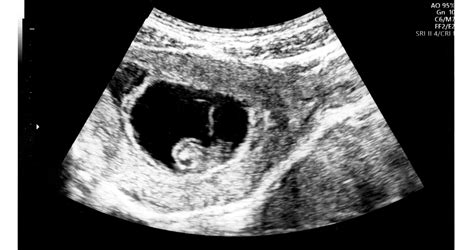

A terhesség megállapítása után a nők többsége izgatottan várja az első ultrahang vizsgálatot. Ez általában a terhesség 5. és 8. hete közé esik. Amikor először ülünk be az ultrahang vizsgálóba, a szívünk a torkunkban dobog. A terhesség korai szakaszában a monitoron megjelenő képek még rejtélyesek lehetnek, de a szakember számára tele vannak információval. A legkorábbi, életet jelző struktúrák között, még a szívverés detektálása előtt, van egy apró, kör alakú képződmény, amely nélkülözhetetlen a csodálatos utazás elindulásához: ez a szikhólyag (más néven vitellusz zacskó).

A szikhólyag általában a terhesség 5. hetében vagy az 5. hét elején válik láthatóvá, amikor a gesztációs zsák átmérője eléri a 10 mm-t. A szikhólyag megjelenése a korai terhességi ultrahangon több, mint egy puszta pont. A szikhólyag egy ideiglenes, membránnal határolt zsák, amely az embrió mellett helyezkedik el. Nevét a madarak és hüllők tojásában található szikre emlékeztető funkciójáról kapta, bár az emberi szikhólyag nem tartalmaz nagy mennyiségű tápláló szikanyagot.

A szikhólyag méretét milliméterben (mm) mérik. Ez a struktúra a 6. és 10. terhességi hét között éri el a maximális méretét, majd fokozatosan zsugorodni kezd, ahogy a placenta veszi át a tápanyagellátás szerepét. A 6. hét körül az ultrahangon egy különleges jelenség figyelhető meg, amelyet „dupla hólyag” jelnek neveznek. Ekkor a gesztációs zsákban egyszerre látható a szikhólyag és az azt körülvevő, de különálló amniális (magzatvíz) zsák. Ez a két hólyag egymás mellett helyezkedik el, és az amniális zsák tartalmazza a fejlődő embriót.